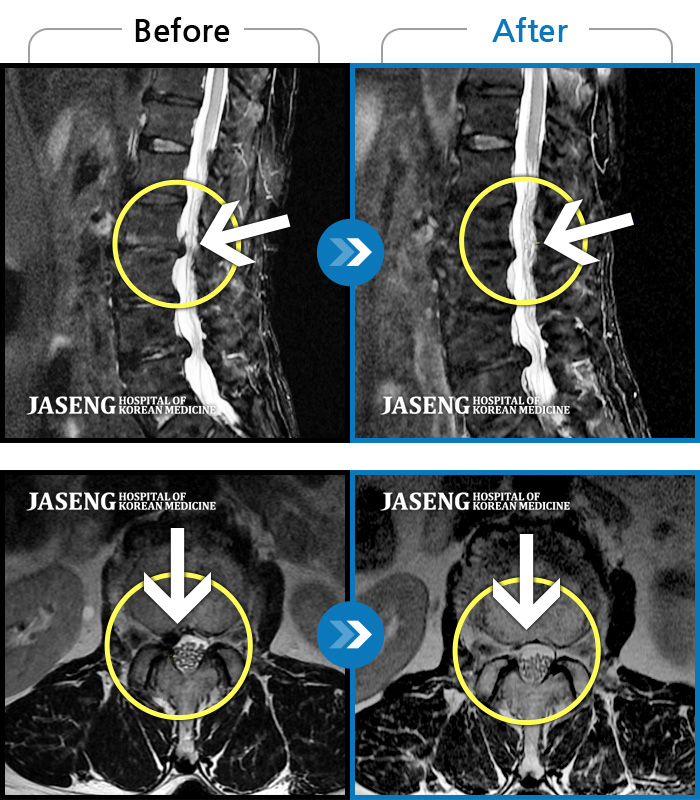

ȯںп Ǹ ǿ ԿǾ, ο ġ ۿ Ƿ ġḦ Ͻñ ٶϴ.